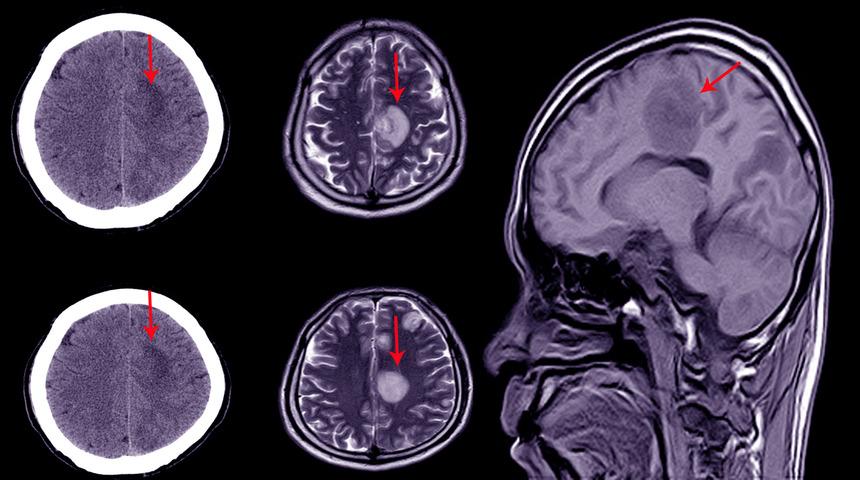

'Hidrosefali nedir?' sorusuna çeşitli cevaplar vermek mümkündür. Beyin içerisinde beyni ve omuriliği besleyen sıvılar mevcuttur. Bu sıvının fazla üretilmesi veya az emilmesi su şişkinliğine sebep olur. Beyinde biriken su şişkinliğine hidrosefali denir. Bu hastalık beyin omurilik sıvısının artması ile oluşan bir hastalıktır.

Beyin ve omurilik sıvısının artması ile ortaya çıkan Hidrosefali hastalığı son derece hassas ve sürekli kontrol gerektiren bir rahatsızlıktır. Her yaş grubunda farklı belirtiler gösterir. Ancak kesin bir tanı konulması için nöral dokunun incelenmesi gerekir.